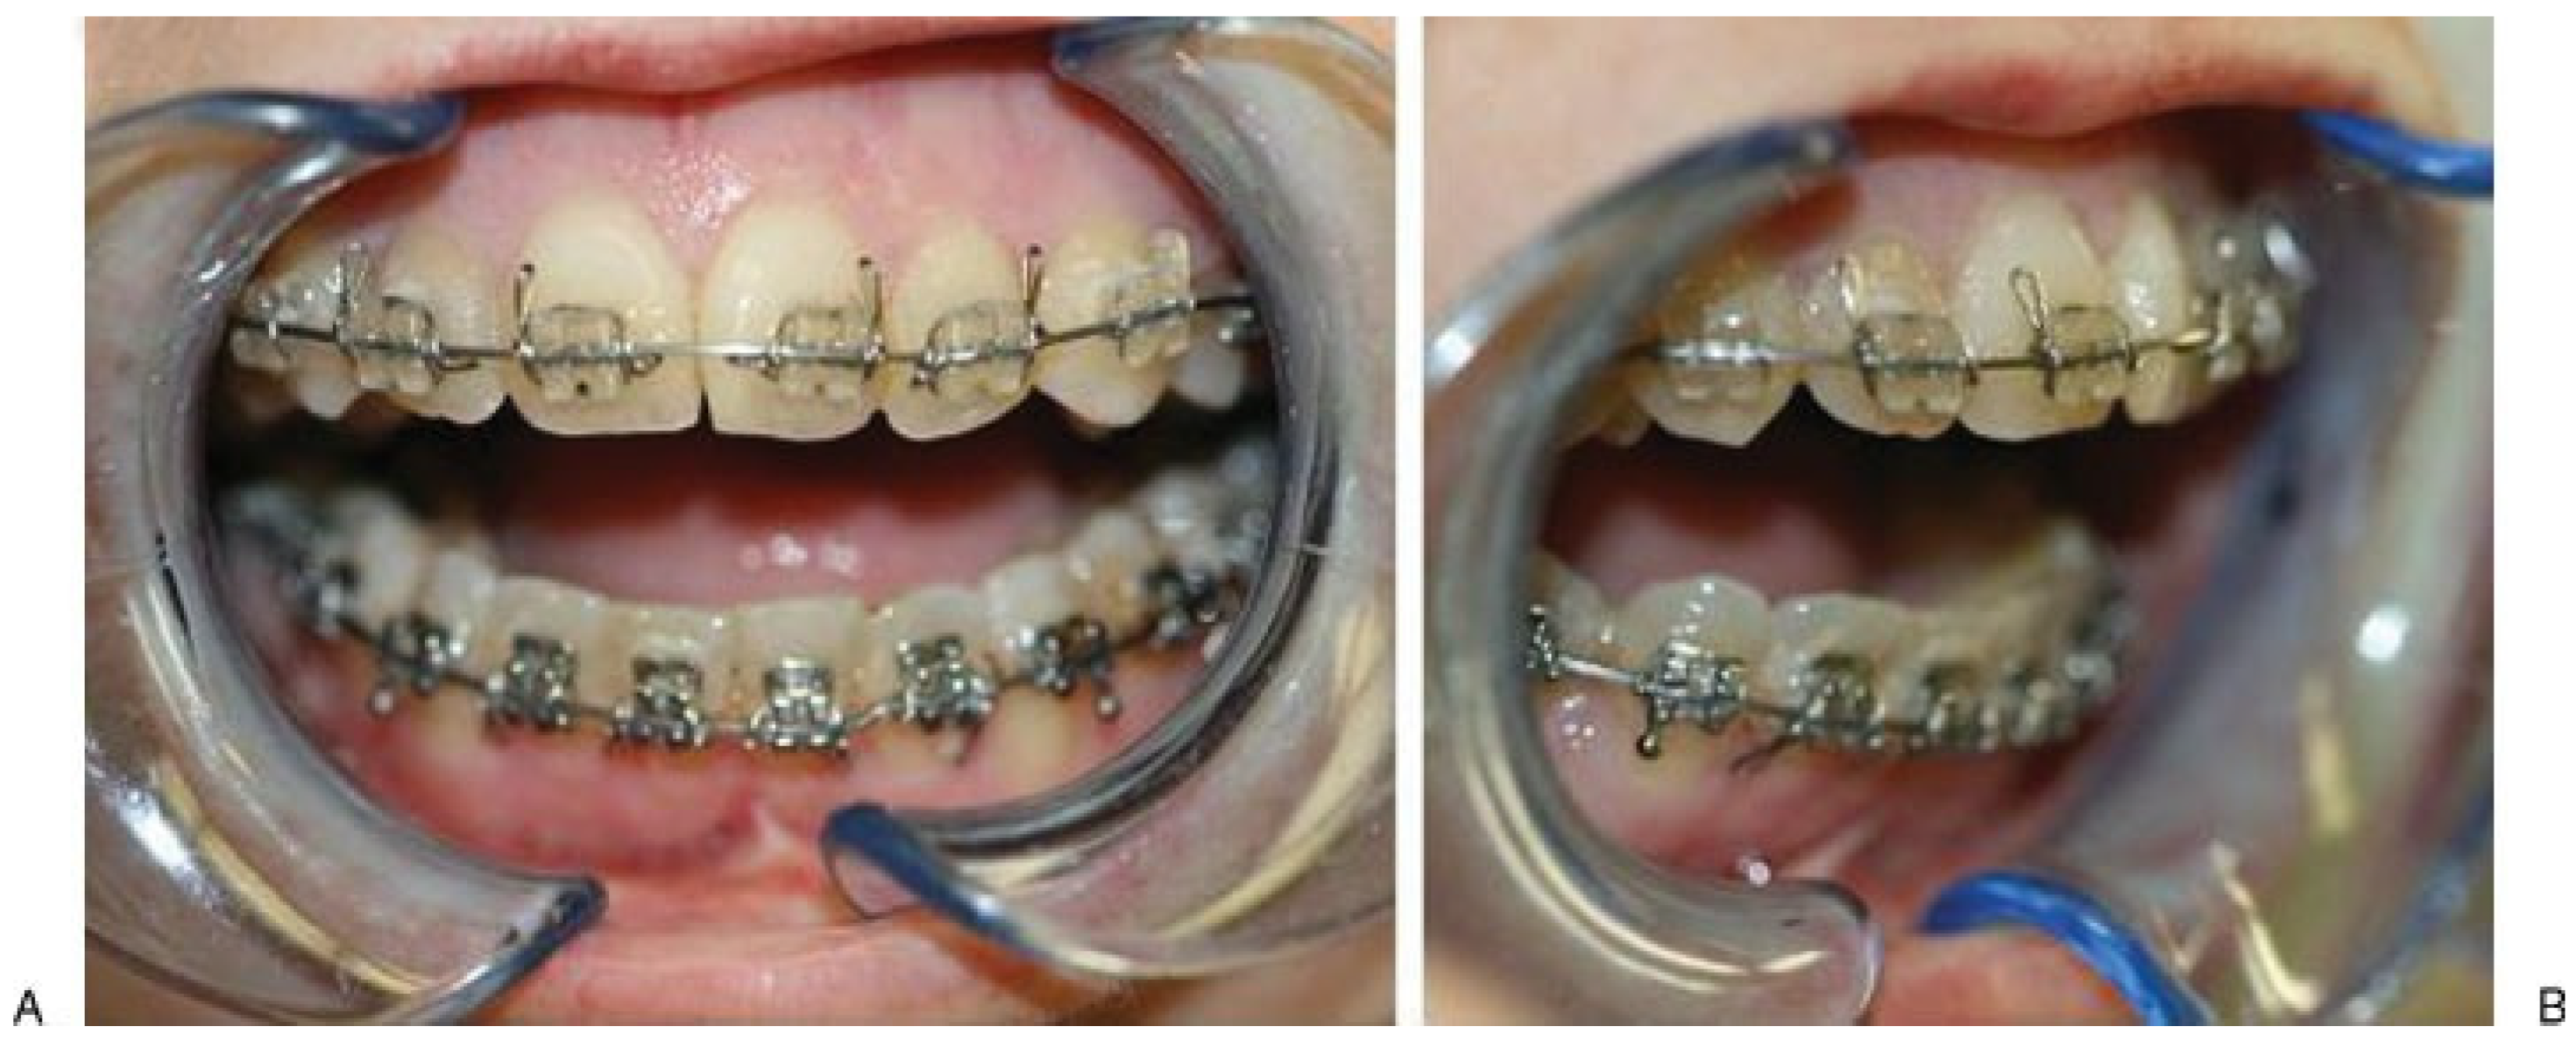

Clinical Examination

Surgical Treatment